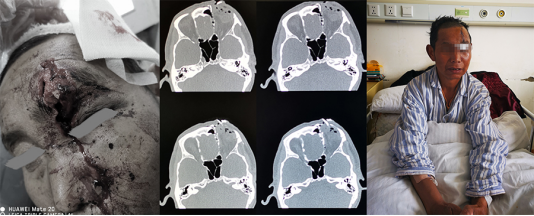

在急诊,牛角巨大的冲击力留下的骇人惨状令人触目惊心:患者眶上缘及额骨骨折脱位外翻皮外,前颅底组织破碎、残缺,筛窦、额窦开放,颅底硬膜缺损,脑脊液外渗,额底脑组织一处盲管伤。

尽快!手术清创缝合

颅底骨折断端把硬膜撕扯残缺不整,正常的组织界限已经没有。完成了脑内挫伤组织的清创。我们在显微镜下仔细寻找着硬膜的断端,游离出1-2mm的空间,予以一期自体筋膜修补,水密试验确保缝合确实。开放的副鼻窦用自体筋膜封闭。双层封闭措施对于开放性颅脑创伤患者的预后改善是有很大帮助的。

此时眼球的眶脂体包膜就在视野之下。也许是患者在牦牛来袭的一瞬间下意识的低头,让眼球躲过了一劫。联合眼科检视解剖上完整无大碍。骨折片回纳固定,重建眶部及颅底结构,不至于术后出现面部的明显塌陷。再美容缝合额面部皮肤,尽可能地减少疤痕。

所幸患者术后恢复顺利没有出现颅内感染、脑脊液鼻漏、复视、眼球活动障碍等并发症,顺利出院。